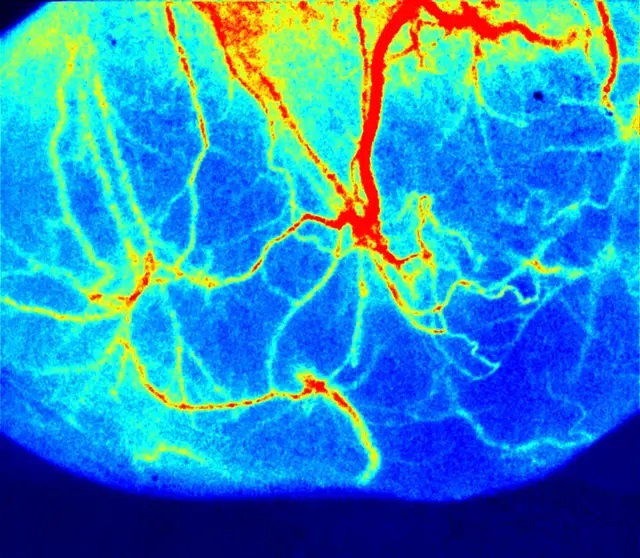

▲C57BL/6腸系膜血流

腸系膜是研究臟器微循環(huán)的良好部位,膿毒癥和急性腹腔內(nèi)炎癥狀況影響內(nèi)臟循環(huán)目前已獲得普遍共識。低灌注是麻醉和危重病的常見特征。譬如低心輸出量狀態(tài)、血管舒張性或低血容量性休克和腹腔室綜合征 (ACS)。在這種情況下,其他重要器官的灌注通常以犧牲內(nèi)臟循環(huán)為代價來維持?赏ㄟ^腸系膜微循環(huán)變化來揭示多種疾病的發(fā)病機理、篩選有效藥物、判斷疾病變化及預(yù)后等。利用瑞沃德激光散斑技術(shù),能清晰的觀察到腸系膜第五級分支,并進行精確定量。